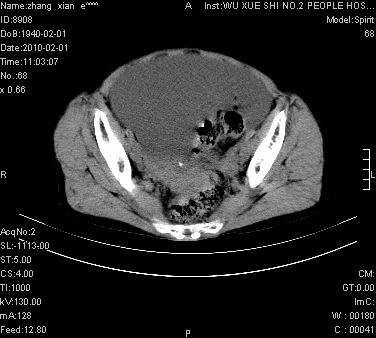

标题: CT24434:70岁 女 腹胀,腹水原因待查 [打印本页]

标题: CT24434:70岁 女 腹胀,腹水原因待查

考虑:1、腹膜转移,大量腹水;

2、脾占位性病变;

3、左侧卵巢占位性病变,建议增强进一步检查。

考虑:1、腹膜转移,大量腹水;2、脾占位性病变;3、左侧卵巢占位性病变,建议增强进一步检查。支持